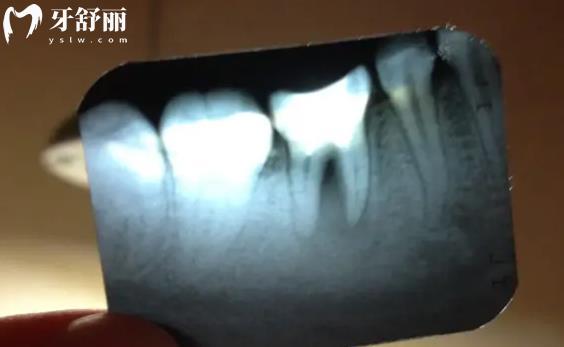

牙齿的结构是一层一层的,只凭借肉眼是很难看到牙齿内部有什么问题的,所以需要拍摄牙片,来看患者埋在牙龈下的牙根、牙齿的内部结构。才能快速发现在外表观察不到的隐蔽情况。

3.根管治疗,牙片是可以看到是否已经感染到牙髓,看牙齿周围有没有黑色的缺损,尤其适合邻面龋的诊疗。

1.根尖片,也叫作小牙片,主要是看单颗或两三颗牙齿情况的龋坏和根尖情况。